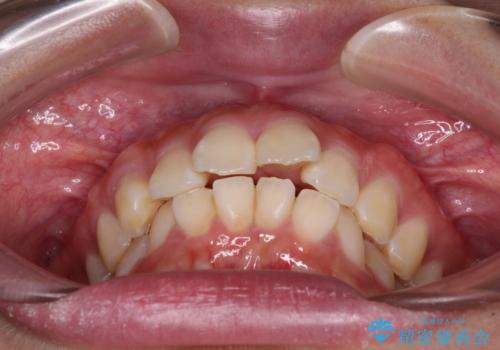

- 前歯部のデコボコと口元が出ているのが気になるとのことで来院された患者様です。

口元の突出感の解消と、このままデコボコを解消するとさらに出っ歯傾向になってしまうことを考慮し、上下左右の小臼歯を抜歯しクリアブラケットにて矯正していくこととしました。